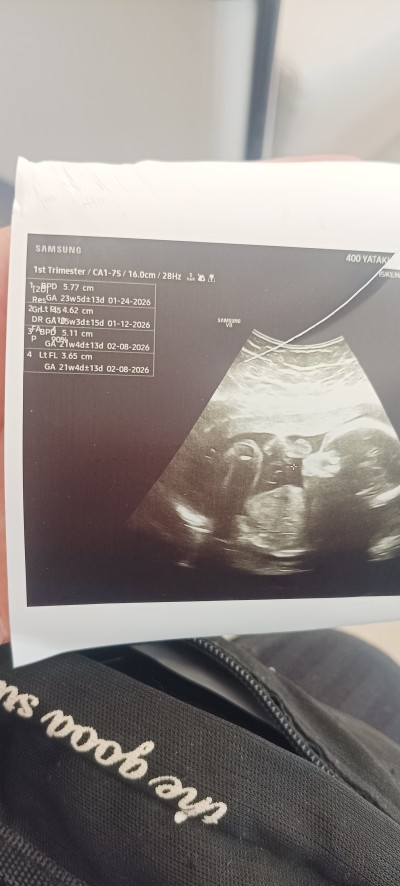

Sevgili hamileler anneler sor um bu aslında

yani bu haftalarda bu ölçümler normal mi

yapay zekaya da sordum ortalama olarak normal falan diyor ama zaten üst üste binmiş gibi ben bir şey anlamadım

doktor da hiçbir yorum yapmadı sadece ölçümleri söyledi daha sonra detaylı ultrason zamanın gelmiş hemen randevu al git dedi

Gebelik haftası 22+3 ortalama olarak

Zaten 22 haftalıkmışsınız ölçümlerde aynı civarda sorun ne anlayamadım

Bi an önce randevu al demesinin sebebi ayrıntılı ultrason haftan geçiyor canım o yüzden,23 haftaya kadar yapılıyor ya o yüzden bi an önce al demiş.ufak tefek ölçüm farkları önemsiz